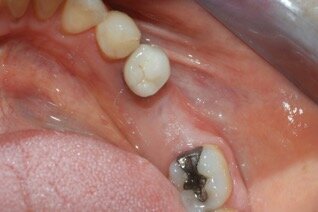

Sei mesi dopo i pazienti sono stati sottoposti ad intervento chirurgico per il posizionamento dell’impianto. Eseguita l’anestesia locale e scollati i lembi a spessore totale in mandibola, è stata eseguita una carotatura per l’analisi istologica della qualità dell’osso (Figg. 4, 5). Nello stesso sito, dopo averlo adeguatamente preparato è stato posizionato un impianto DAE 4 x 11,5 mm al livello dell’osso crestale (Fig. 6). Successivamente sono stati suturati i lembi (Seta, Ethicon 4.0, Johnson & Johnson Medical, New Brunswick/NJ, USA). Infine, prescritti un antinfiammatorio (Nimesulide 100 mg, 2 volte al giorno per 3 giorni), un analgesico (Paracetamolo 500 mg, 1 compressa ogni 8 ore per 3 giorni), e clorexidina 0.12% durante la fase post-operatoria insieme a istruzioni complete all’igene orale. La sutura è stata rimossa a 10 giorni dall’intervento chirurgico. Sei mesi dopo, l’impianto è stato protesizzato con una corona singola avvitata in metallo-ceramica. A 3 mesi e a 3 anni sono state eseguite le radiografie periapicali parallele.

Le radiografie eseguite immediatamente dopo l’intervento chirurgico con la tecnica GBR hanno indicato che l’alveolo post-estrattivo era stato adeguatamente zeppato con granuli di osso bovino decellularizzato (Fig. 7). Il richiamo a 6 mesi, ha mostrato tessuti molli in buona salute senza la presenza di segni di infiammazione (Fig. 8). La radiografia periapicale ha mostrato la perfetta guarigione dell’alveolo post-estrattivo (Figg. 9, 10). Anche durante l’esposizione ossea per il posizionamento dell’impianto, l’osso appare in buona salute e non sono presenti granuli di biomateriale non integrato. La membrana di pericardio bovino è completamente riassorbita (Fig. 11).